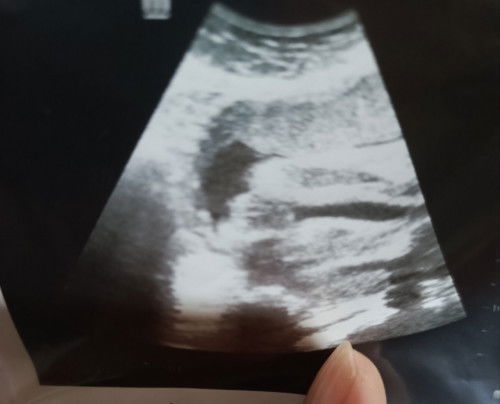

Tumpang tanya mommy2, kalau scan macam ni ada harapan ke dapat girl?

Scan jantina baby

bukan lg ada harapan sis. tp mmg girl ne haha. nmpk belahan burger nya dsituu

saya 31w scan pgi ni . mcm ni juga bentuk nya.. hehehe

yang tu sis

mcm garis2